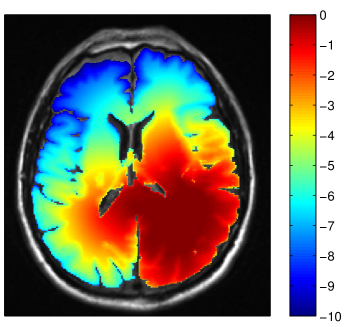

In the manual delineation of the CTV used in the clinical plan, it is incorporated that the falx represents an anatomical barrier for the migration of tumor cells. Hence, the isotropic target expansion was trimmed manually. In the tumor growth model, the falx is modeled via a layer of CSF and is automatically accounted for through the assumption that tumor cells only migrate within white and gray matter. However, the corpus callosum connects the two hemispheres of the brain. The tumor growth model describes the migration of tumor cells through the corpus callosum (see figure 3 and 5a). As a consequence, the target volume based on the growth model is extended into the contralateral hemisphere. Figure 5a shows the tumor cell density overlaid on the coronal T1 gadolinium image. This illustrates the three-dimensional modeling of tumor spread via the model, including areas superior to the corpus callosum. This is not consistently accounted for in the manual CTV. In the manually drawn target volumes, the target is slightly extended into the contralateral hemisphere on the slices that show the corpus callosum, but not on the slices located superiorly and inferiorly (figure 5b). In the model derived target volumes, the target is extended further into the contralateral hemisphere, and the spread of tumor cells in superior-inferior direction beyond the corpus callosum is modeled.

Refer to caption

Figure 5: (a) Log tumor cell density overlayed on the coronal T1 image showing spread of the tumor in the contralateral hemisphere (λw=4.2subscript𝜆𝑤4.2\lambda_{w}=4.2 mm and Dw/Dg=100subscript𝐷𝑤subscript𝐷𝑔100D_{w}/D_{g}=100). (b) Comparison of manual CTV (green) and model based CTV (red) (same contours as in figure 4.